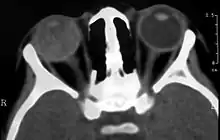

Визуализирующие исследования, такие как ультразвуковое исследование (УЗИ), компьютерная томография (КТ) и магнитно-резонансная томография (МРТ) могут помочь диагностике. На УЗИ, болезнь Коутса выглядит как гиперэхогенная масса в задней части стекловидного тела без задней акустической тени; также наблюдаются кровоизлияния в стекловидное тело и субретинальную область[8][9].

На КТ, гиперплотный шар появляется на фоне обычного стекловидного тела из-за белкового экссудата, который может уничтожить стекловидное тело на поздних стадиях заболевания. Передний край субретинального экссудата усиливается с контрастом. Поскольку сетчатка фиксируется сзади оптического диска, это усиление имеет V-образную конфигурацию[4].